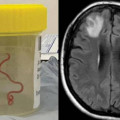

Ֆոտո